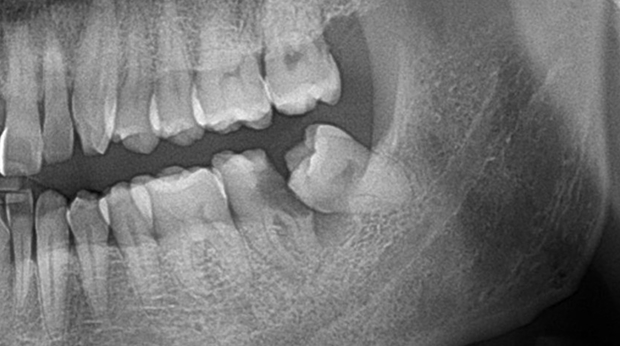

매복 사랑니 발치

임플란트와 사랑니 발치는 외과적 시술로 잇몸을 절개하는 외과적 시술은

짧으면 짧을 수록 시술 후 붓기와 통증이 최소화됩니다.

치과의사 경력 14년차 구강외과 전문의가 빠르고 안전하게, 아프지 않게 수술해 드립니다.